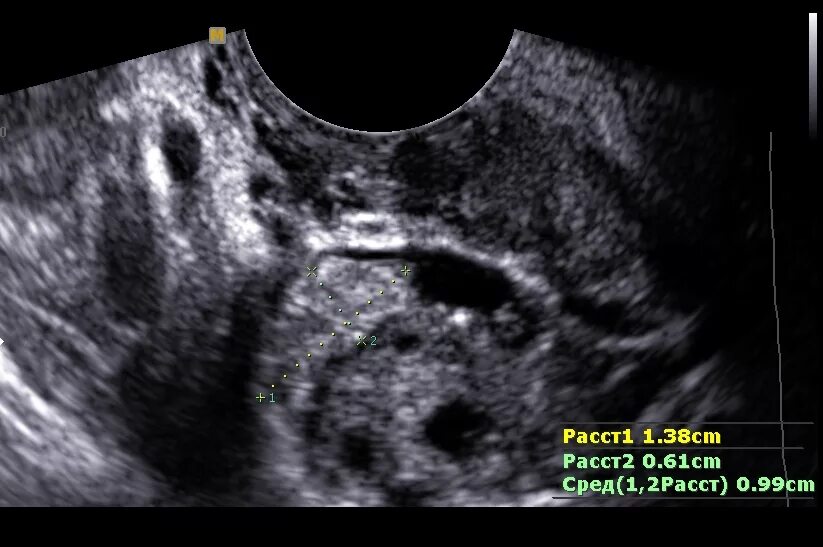

Можно ли на узи увидеть внематочную беременность